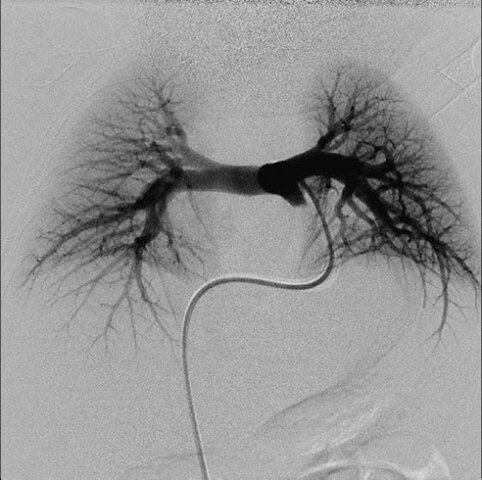

• Angiograma pulmonar

Angiograma pulmonar

Lopo de Carvalho realizó el primer angiograma pulmonar por punción venosa del miembro superior. (Chen et al., 2014).